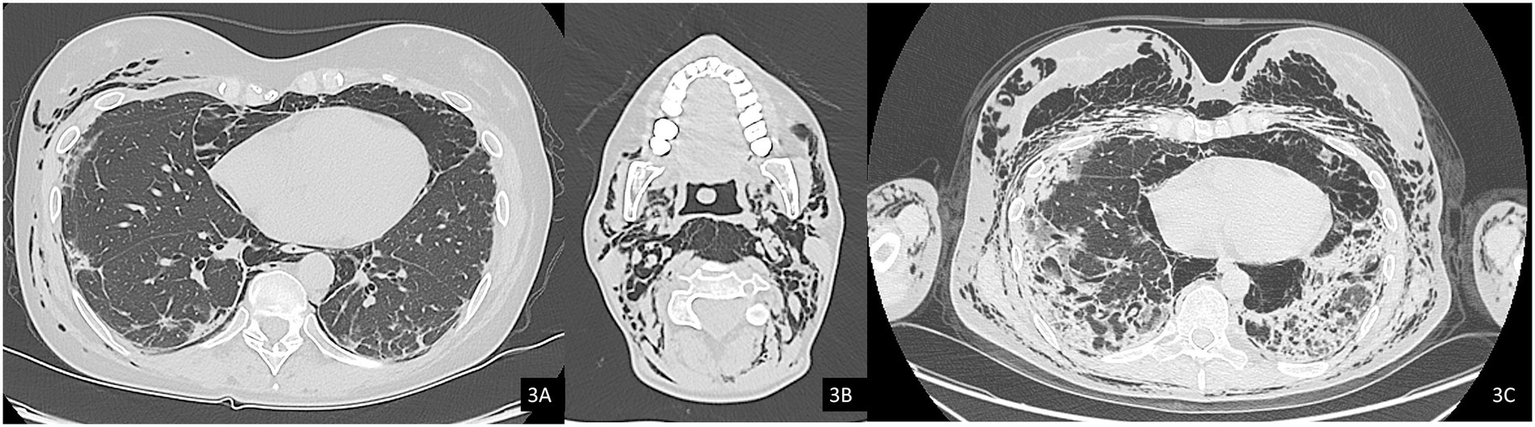

The chest HRCT performed at the end of April 2025 (Figure 4) demonstrated complete resolution of the previously observed pneumomediastinum. When compared with the August 2024 scan (Figure 4C), imaging revealed progression of fibrotic interstitial changes. Although comparison with interim scans was limited by the presence of pneumomediastinum, there were no current radiological signs of active inflammatory disease.

Figure 4. Axial (A) and coronal (B) chest CT images showing resolution of the pneumomediastinum and subcutaneous emphysema. Note the presence of interstitial lung disease (ILD) with a mixed NSIP/OP pattern and fibrosing features, including coarse reticulations, parenchymal distortion with traction bronchiectasis, and volume loss. (C) Comparison with a previous CT scan from 2024 demonstrates clear radiological progression of ILD.